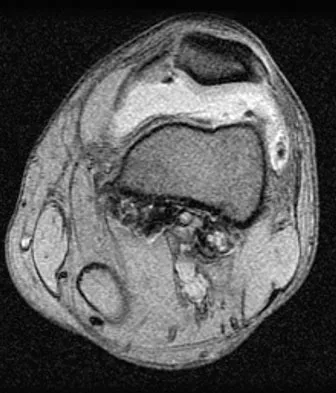

The arrow in the axial T1-weighted MRI scan shown in Figure 18 is pointing to which of the following structures?

Explanation